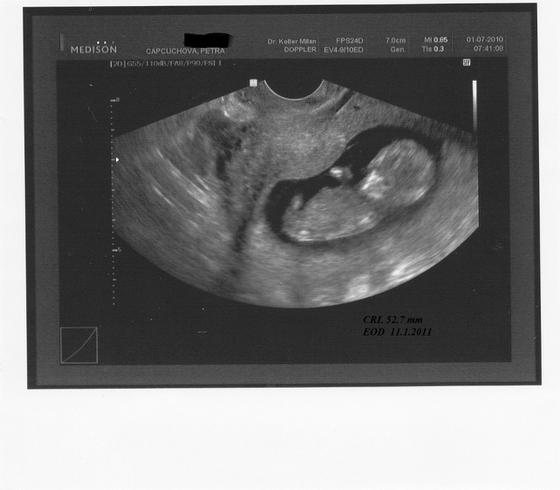

1.7.2010 v 11+2tt jsme dostali těhotenskou průkazku a boxík se vzorky a kuponky na slevy. Mimískovi krásně bije srdíčko a je 5,2 cm velký. Přes utz nám zamával,,abych pomalu, ale jistě, tomu začala věřit, že jsem těhotná a budu pro něj tou nejdůležitější osůbkou v životě. 15.7. nás čeká screening, tak snad vše dopadne dobře, jinak bych musela do Ústí na amnio ☹ , bojim, bojim!